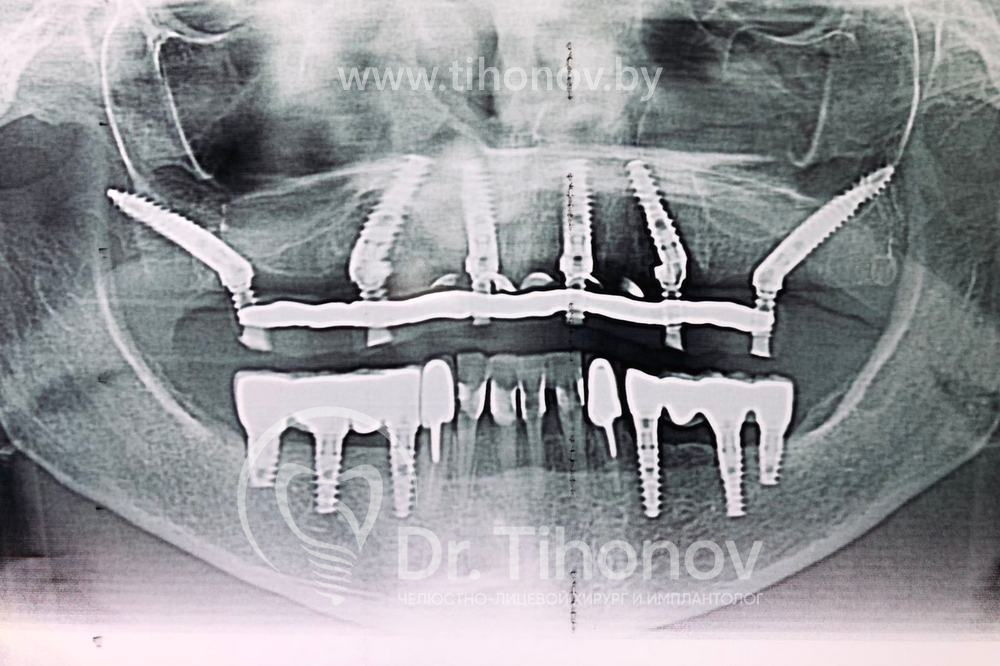

Кейс №5 - Установка 6 имплантов и несъемного протеза за 4 дня

02 Сентября 2020 Установка протеза по методике All-on-6

На очной консультации после обследования полости рта и изучения данных 3D-исследования челюстей совместно с пациенткой был выработан план реабилитации верхней челюсти с использованием современной и эффективной методики протезирования All-on-6 (все на 6-ти).

Была проведена операция на верхней челюсти, во время которой:

• удалены несостоятельные металлокерамические протезы зубов,

• удалены разрушенные корни и все имеющиеся очаги воспаления,

• установлены 6 имплантатов,

• в последующие 4 дня изготовлен и зафиксирован несъемный эстетичный и функциональный протез.